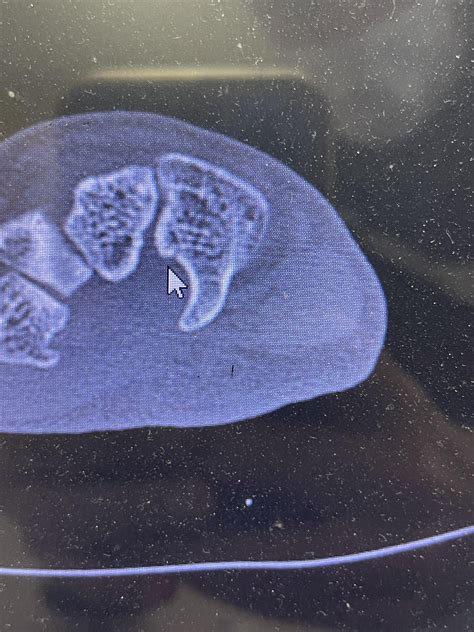

Diagnosis of Hook of Hamate Injuries

Diagnosing a hook of hamate injury typically involves a combination of physical examination and imaging tests. A healthcare provider will perform a thorough evaluation, including:

• Physical Examination: The doctor will assess the wrist for tenderness, swelling, and range of motion. Specific tests, such as the hook of hamate test, may be performed to identify the source of the pain.

• Imaging Tests: X-rays, CT scans, or MRI scans may be ordered to visualize the hook of hamate and identify any fractures or other abnormalities.